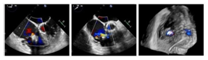

手术在患者全麻状态下进行,经股静脉入路,在经食道超声心动图和X射线引导下将DragonFly-T™瓣膜夹器械输送到右心室,捕捉和钳夹三尖瓣前叶和隔叶并关闭瓣膜夹,利用经食道超声心动图反复确认手术效果后,zui终释放三尖瓣瓣膜夹,术中共植入3枚瓣膜夹,瓣膜夹位置和功能良好,三尖瓣反流分级由术前的5+(图2)降至术后即刻的1+(图3),肝静脉血流明显改善(图4),手术顺利完成。

图2.术前经食道彩色多普勒超声图

图3. 术后经食道彩色多普勒超声图